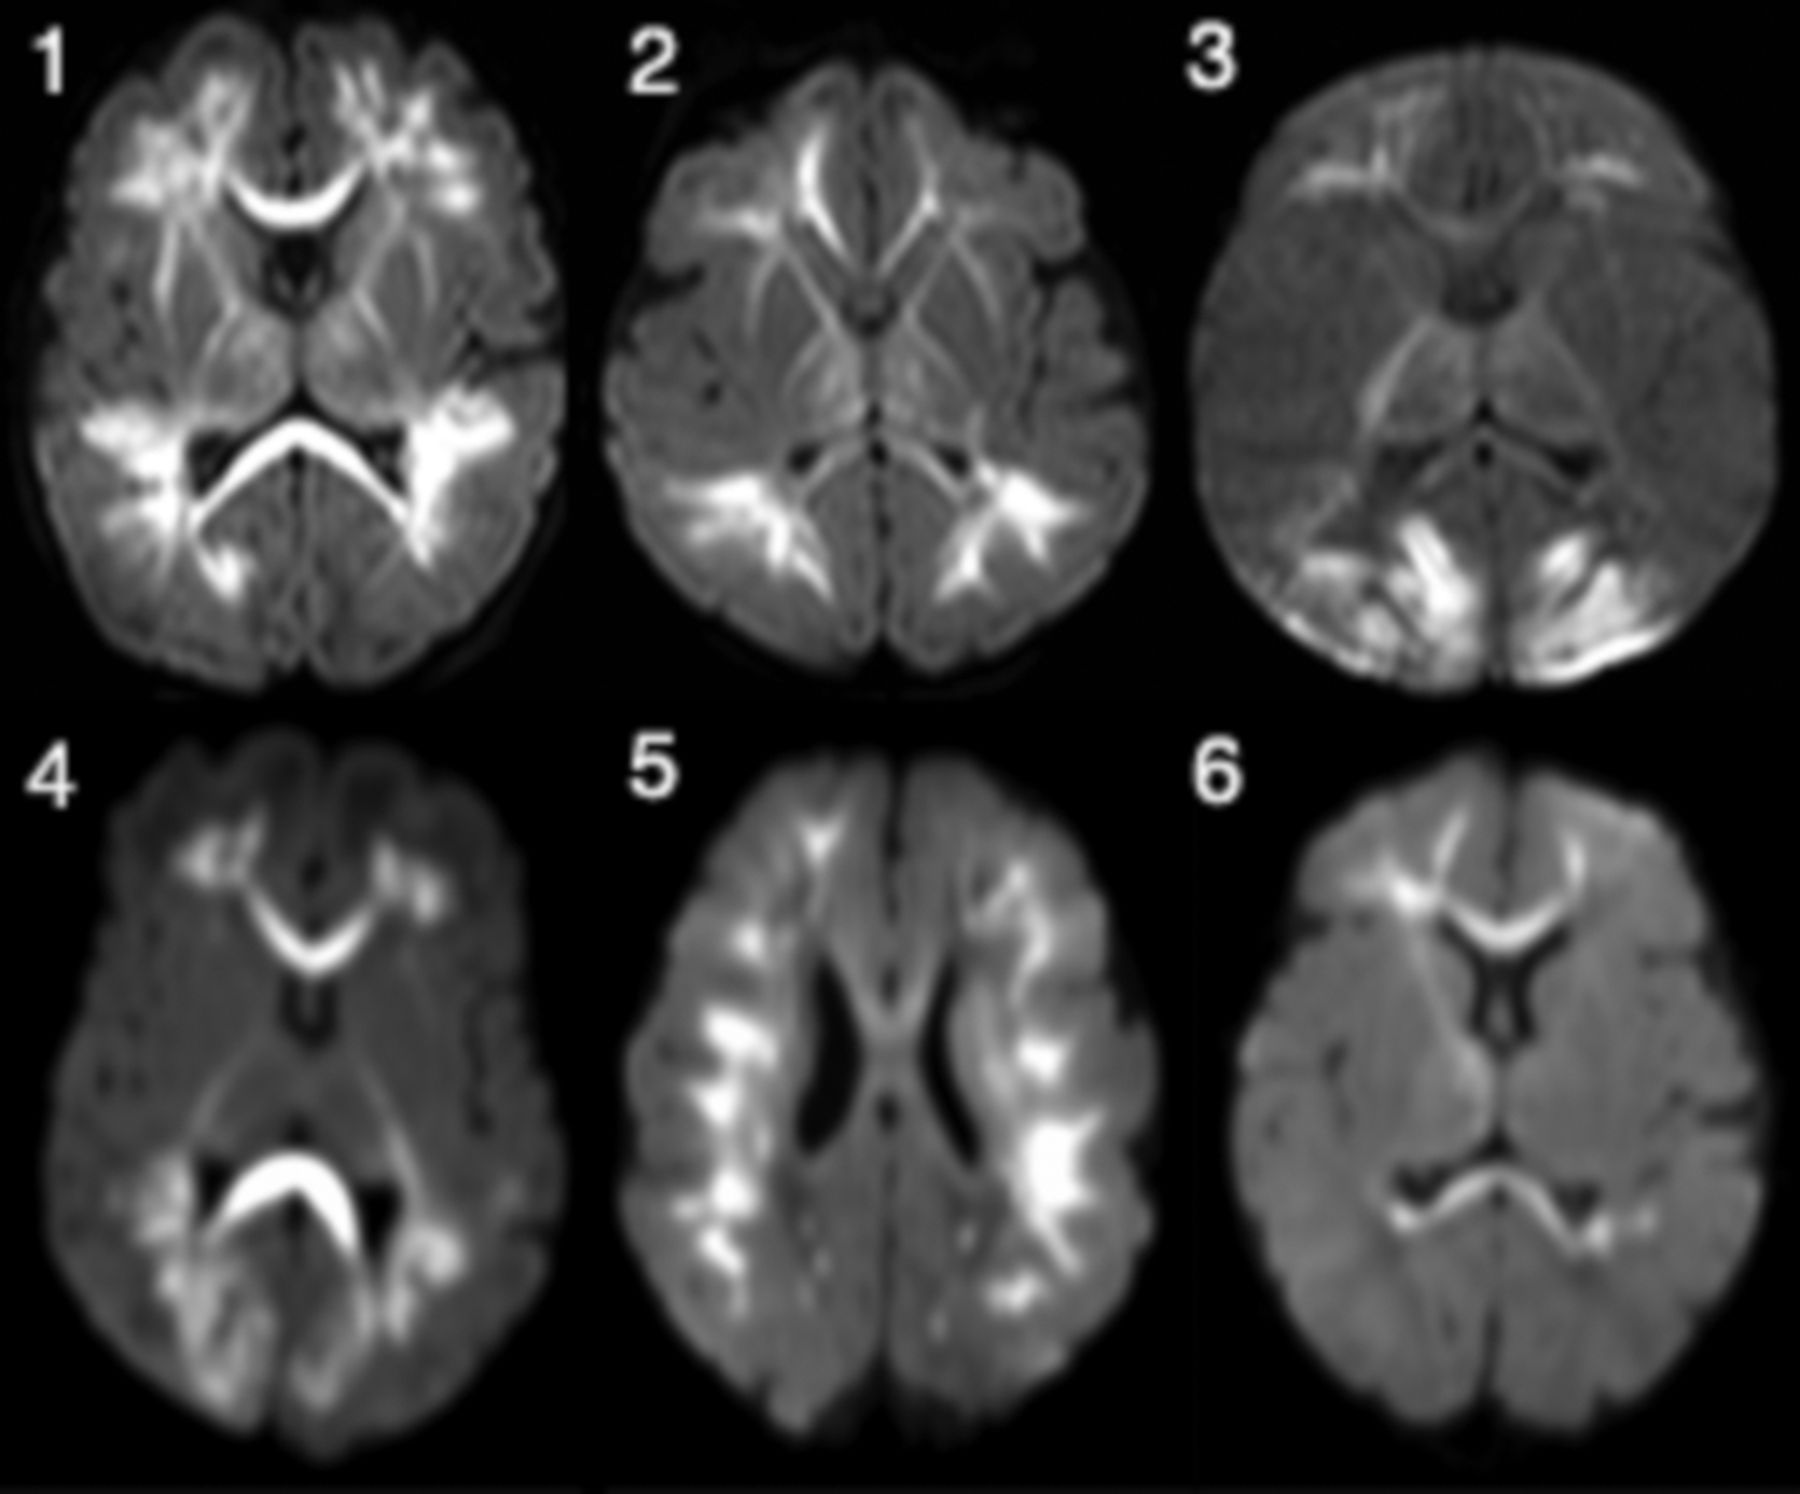

The most characteristic finding in all cases was diffuse/multifocal frontal-predominant subcortical white matter and callosal involvement with associated low diffusivity (Fig 1). The thalami were involved in all cases to varying degrees. The 2/6 with striking occipital involvement were also the only cases with cortical signal abnormality (also in the occipital lobe). No cases exhibited signal abnormality within the basal ganglia, hippocampi, brain stem, and cerebellum. Branching T1 and T2 shortening along the distribution of the deep medullary veins was noted in 4/6 (Fig 2). In 2/6, these foci were identified on either T1- or T2-weighted imaging but not both. One patient (patient 4, Fig 2) had mild diffuse white matter T2 prolongation, even considering the premature myelination pattern. Scant susceptibility foci consistent with hemorrhage or mineralization were noted in the periatrial white matter in 1/6. Of the 3/6 who underwent MR spectroscopy, only one had elevated lactate in the basal ganglia. Postcontrast, MRA, and MRV results were normal.

Axial diffusion-weighted images in patients 1–6 (infants with HPeV infection) demonstrate low diffusivity variably involving the periventricular white matter with frontoparietal predominance and also involving the corpus callosum, thalami, and internal and external capsules. Patients 3 and 4 exhibit greater involvement of the occipital white matter and the occipital cortex. Patient 5 shows more confluent involvement of the subcortical white matter.